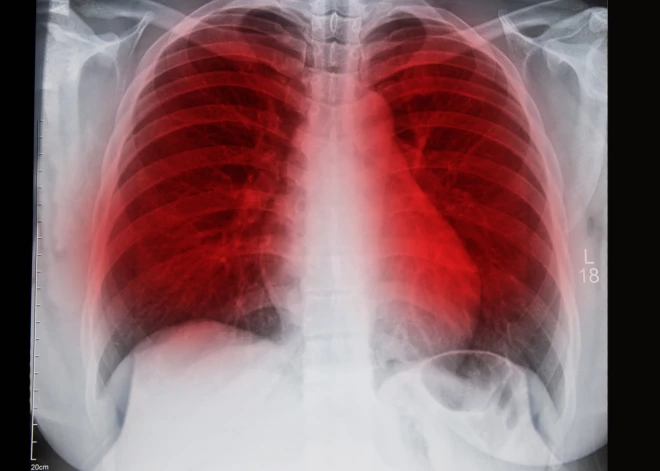

Zinātnisks atklājums, kas varētu krietni samazināt mirstību no plaušu vēža

Plaušu vēzis ieņem vienu no pirmajām vietām saslimstības ziņā un pārliecinoši ir pirmajā vietā mirstības ziņā, jeb, tēlaini izsakoties, plaušu vēzis ir lielākais „slepkava” starp visām onkoloģiskajām slimībām. Diemžēl ļoti bieži šo audzēju atklāj jau vēlīnā stadijā, kas savukārt sasaucas ar plaušu vēža slimnieku dzīves ilguma jeb dzīvildzes rādītājiem. Katrs ceturtais onkoloģijas slimnieks mirst no plaušu vēža.